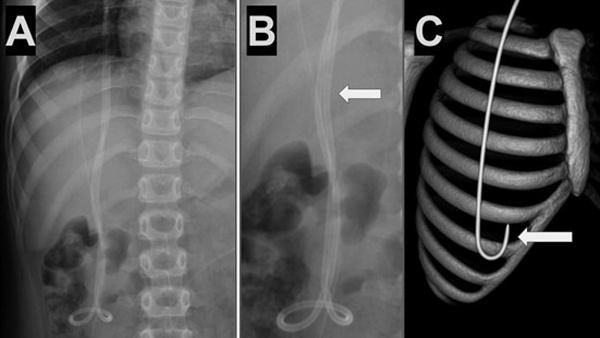

Caso 2. Paciente femenina de 8 años con antecedentes de hidrocefalia congénita y colocación de DVP al mes de vida que presentó cefalea y vómitos. Tomografía de cerebro simple evidenció ventrículos dilatados en comparación con estudios previos. Radiografía de sistema mostró la punta del catéter distal fuera de la cavidad peritoneal (Figura 2).

Figura 2. Caso 2: A) Se observa Rx de tórax y abdomen (frente) con catéter distal a nivel abdominal con migración retrógrada. B) Magnificación de Rx de abdomen que evidencia catéter en doble caño con signo radiológico del “caño de escopeta” o “signo del anzuelo” (flecha blanca) C) Imagen esquemática representando la migración retrógrada de la punta de catéter distal (flecha blanca).